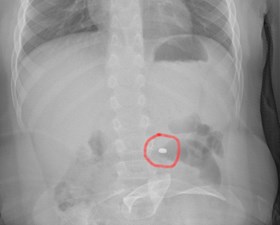

Bambino ingoia pila a bottone, estratta in sala operatoria

La dott.ssa Di Stefano, direttore Pediatria e PS pediatrico: rischio danni, attenzione agli alloggiamenti dei giochi